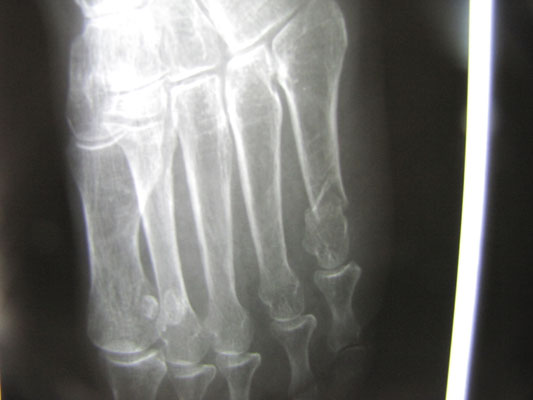

○ アスリートの骨折 ラクビー部

日々ハードな練習と試合をこなしている学生の症例です。

今回は足関節を捻挫して来院しましたが、腫脹(はれ)が強くレントゲン検査を依頼しました。

足首の捻挫に伴う骨折は認められませんでしたが、過去に何か所も骨折をしていたことが判明しました。

親指の種子骨と言われる石ころの様な骨が割れています。第3中足骨が骨折しています。くるぶしの外側の

外果(がいか)に小さな骨の破片があり、やはり骨折です。

スポーツの現場では休むことができません。一般人であればギプスをして一ヶ月休めばよいのですが、短い学生生活の中でシーズンもやはり短いものです。この症例の様にギプスも何もしないで痛みが取れてしまう骨折もあります。